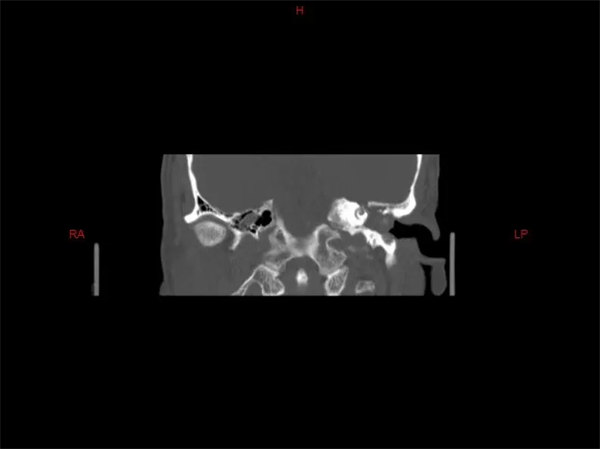

患者白先生(化名),近兩年來因為左耳反復流膿、聽力下降,近3個月又出現左眼閉合不全的癥狀,隨來我院耳鼻喉科就診。科室為其行顳骨CT檢查,結果顯示:患者左側顳骨巖部迷路上型膽脂瘤,侵犯左側內聽道底、耳蝸、前庭、鼓室、乳突、中顱窩底。耳鼻喉科副主任醫師章松林帶領團隊認真完善術前準備,精心設計手術方案,計劃為患者實施經耳蝸徑路左側巖部膽脂瘤切除、耳大神經移植面神經修復、腹部取脂肪左側中耳封閉術。

手術如期開展,術中見患者左側顳骨巖部膽脂瘤,侵犯范圍與術前評估基本相符,膽脂瘤包裹面神經垂直段、錐曲段、水平段及膝狀神經節,其中水平段與膝狀神經節處破壞顯著,遂取耳大神經橋接面神經。術后患者順利出院繼續面神經康復訓練。